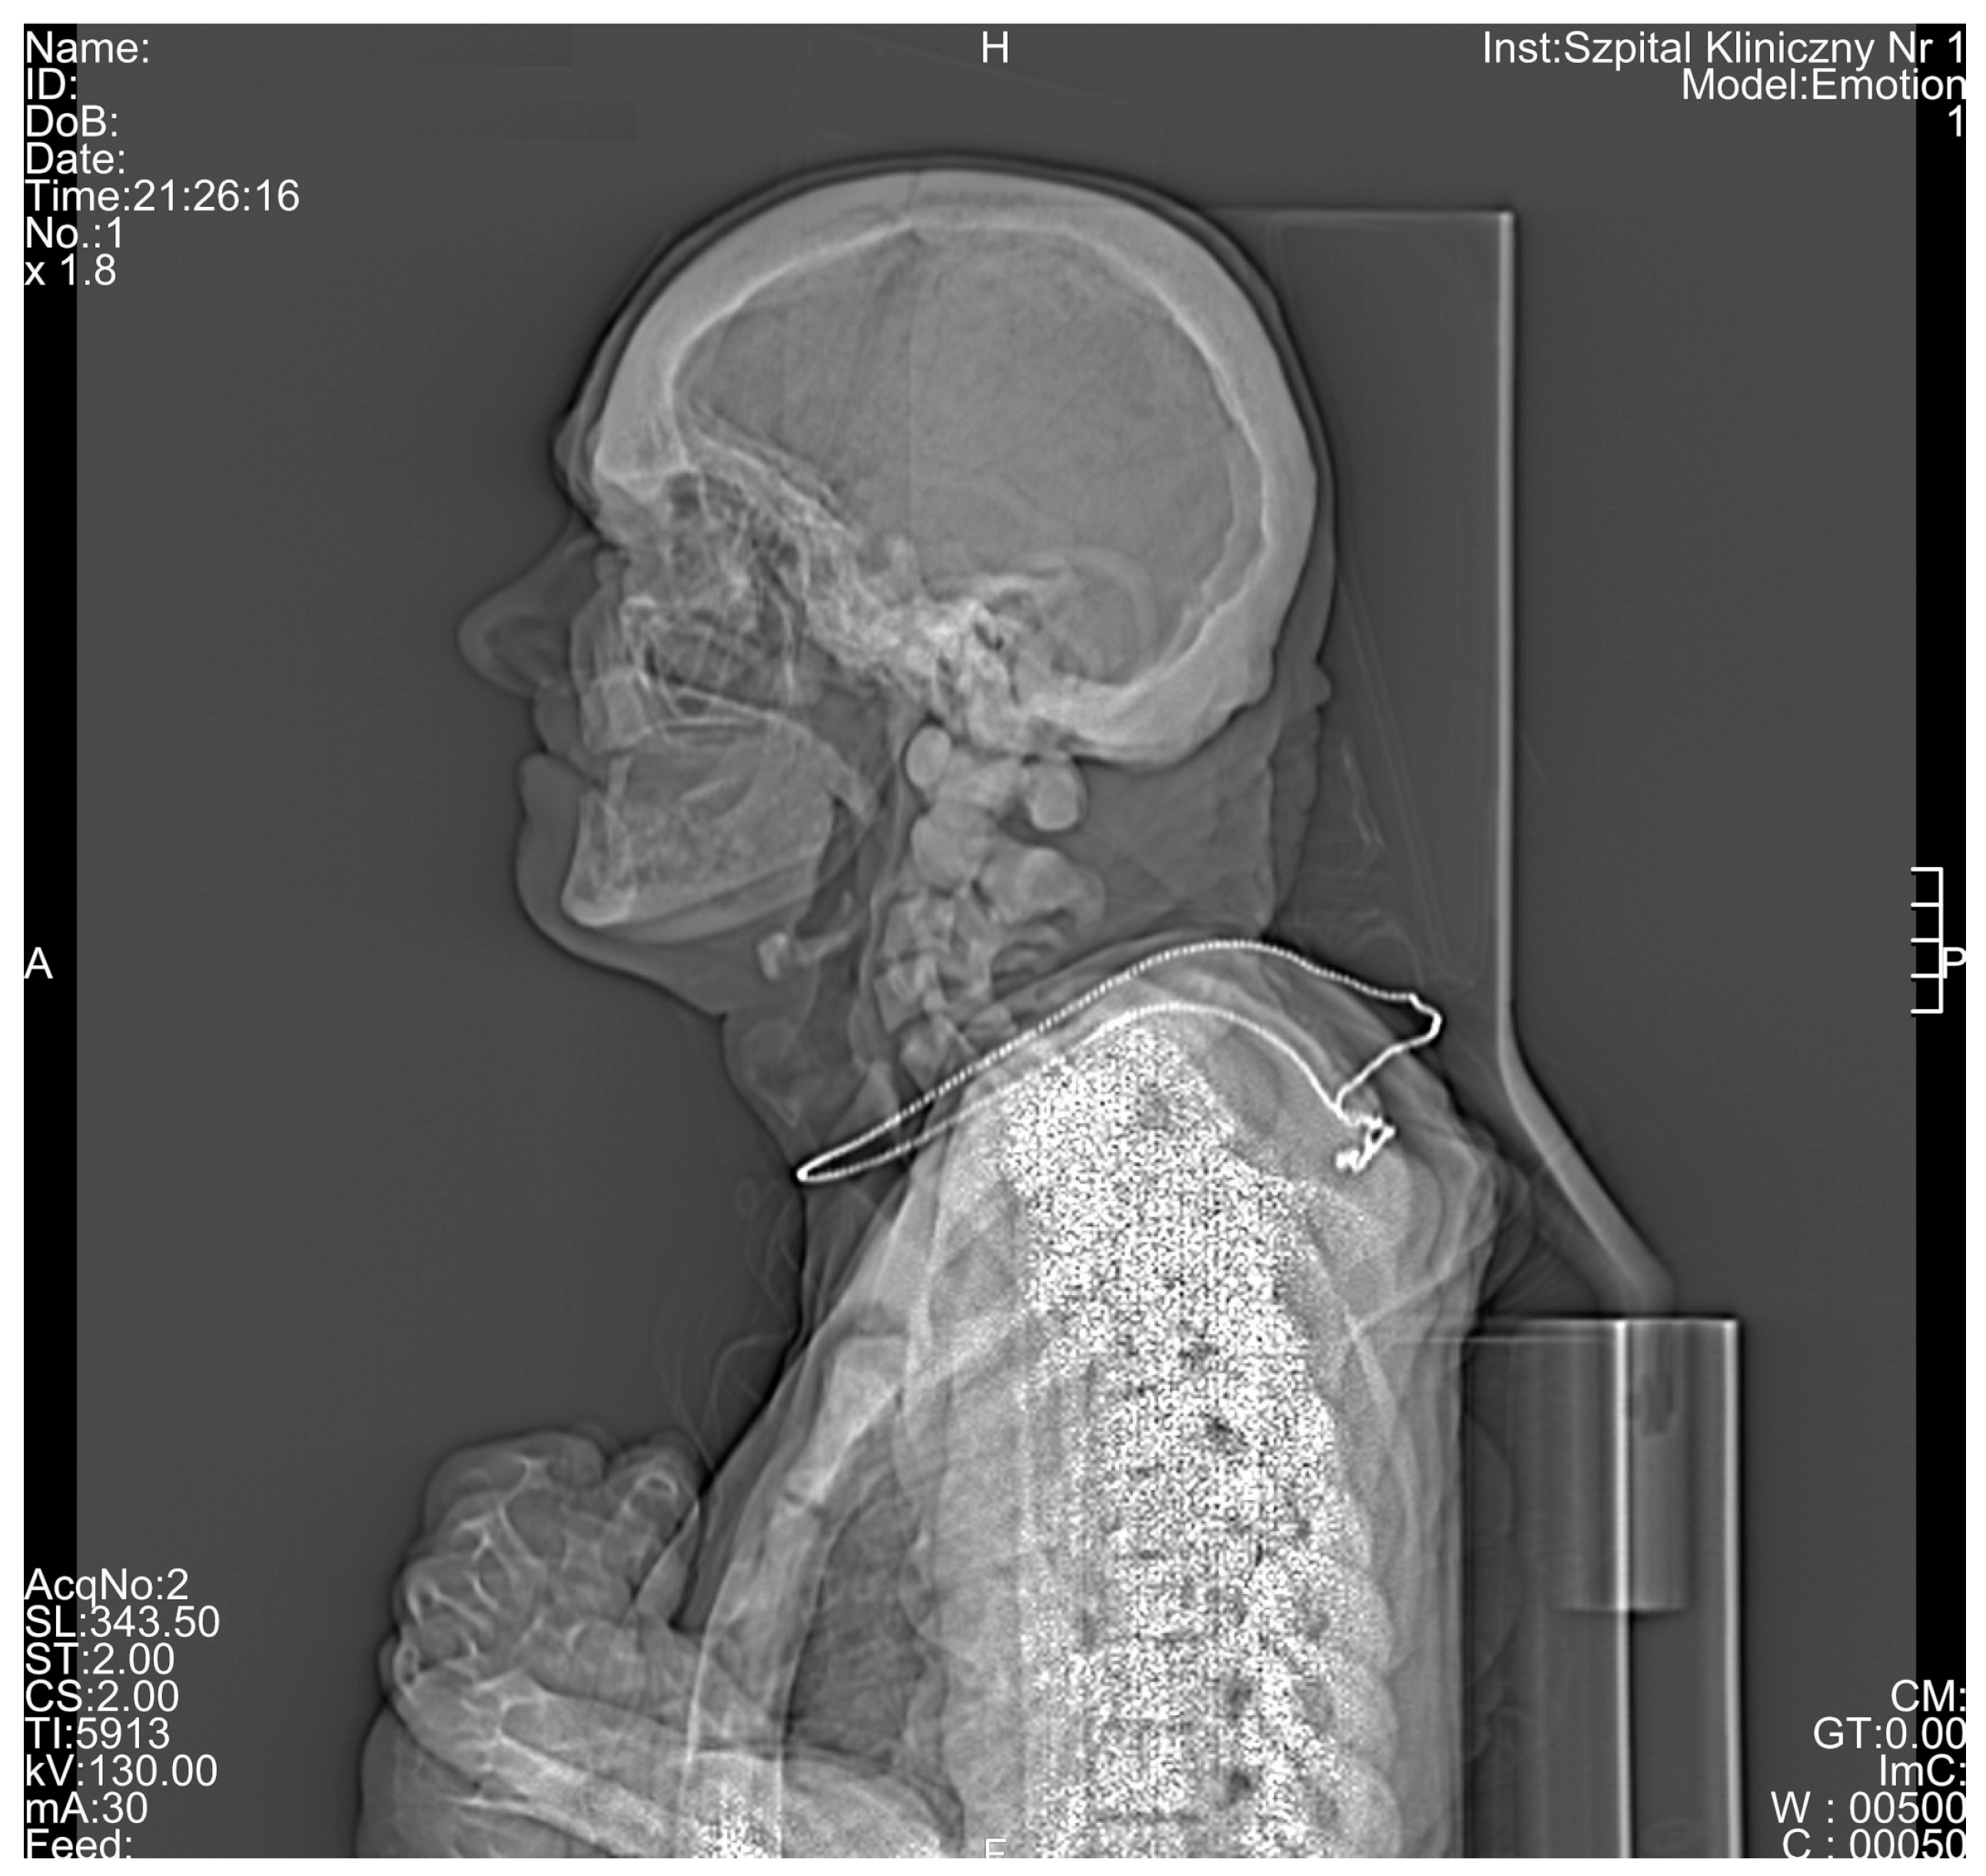

| Cranium | |||||

| 50% of cranium height | - | - | - | - | 2.111 |

| Radiological Feature | ADO Type I | ADO Type II | ADO Type III | Presented Case |

|---|---|---|---|---|

| General osteosclerosis | + | – | + | + |

| Skull vault osteosclerosis | + | – | + | + |

| Skull base osteosclerosis | – | + | – | + |